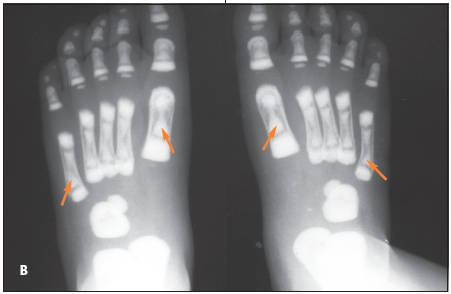

The child has osteopetrosis. The radiographs show diffuse osteosclerosis and dramatically increased bone density throughout the axial and appendicular skeleton. There is diffuse bone sclerosis in the hands with widening of the distal radial metaphyses (A, arrows) and a "bone-within-a-bone appearance"--typical of osteopetrosis--in virtually all the metacarpals and phalanges. Bone sclerosis is also apparent in the feet; the bone-within-a-bone appearance is most prominent in the metatarsals (B, arrows). A chest radiograph demonstrates diffuse bone sclerosis and numerous old fractures of the anterolateral ribs bilaterally (C, arrows).